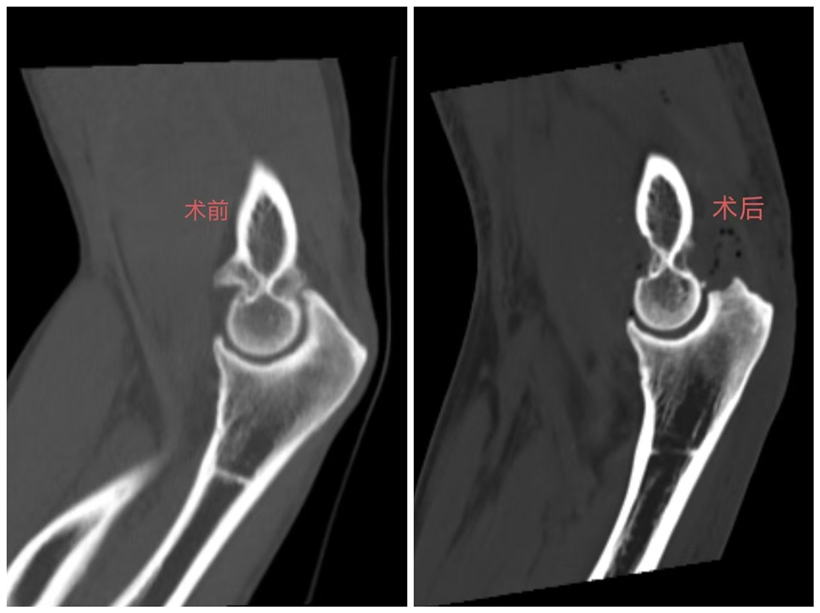

术前术后影像对比图。

术前,该患者的手臂无法正常屈伸;术后,肘部疼痛明显缓解、手臂屈伸功能显著改善。